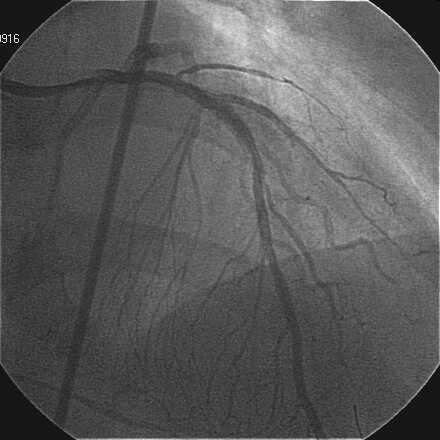

Crush���KBT.

|

|

|